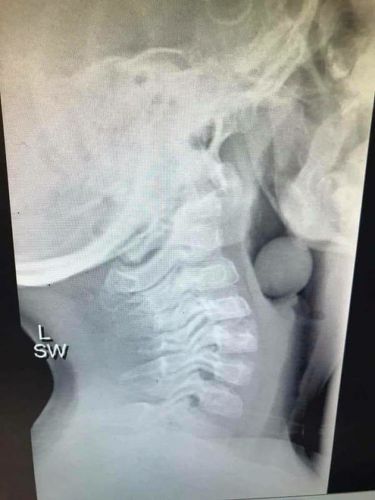

La ingesta de uvas es ni más ni menos que la tercera causa más común de ahogamiento por comida para los niños menos de 5 años. Las vías respiratorias son aún pequeñas a esas edades y sus dientes no están lo suficientemente desarrollados para conseguir un masticado idóneo, además de que lógicamente son más propensos a distraerse...